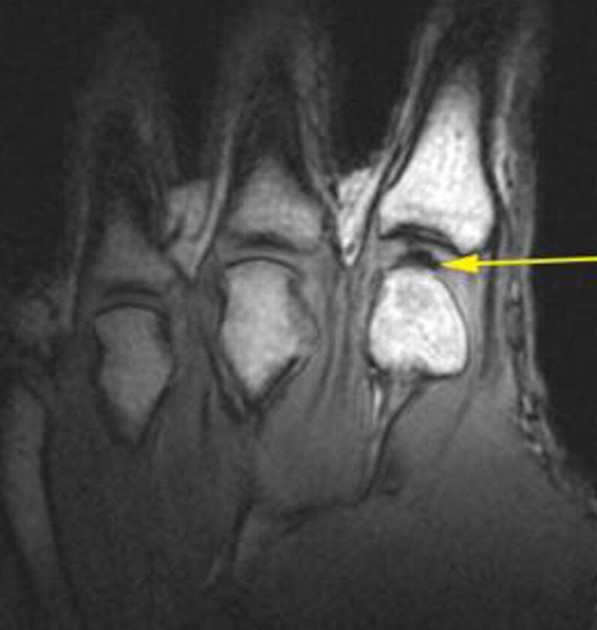

ஆமாம். X-Ray, MRI scans மூலம் மூட்டு எலும்பு தேய்ந்துள்ளதா, cartilages பழுதடைந்துள்ளதா, ligament வலிவிழுந்துள்ளதா என்று கண்டுபிடிக்கலாம். அதற்கேற்ப தேவையான சிகிச்சைகளை செய்வது நல்லது. மனப்பயம் கொண்டு உடற்பயிற்சிகளை கைவிடக்கூடாது. வைத்தியர்கள் சொல்லும் ஆலோசனைகளை கேட்டு அதன்படி நடந்தால் வலிகளை ஓரளவு கட்டுப்படுத்தி நாளாந்த வாழ்க்கையை ஓட்டலாம்.